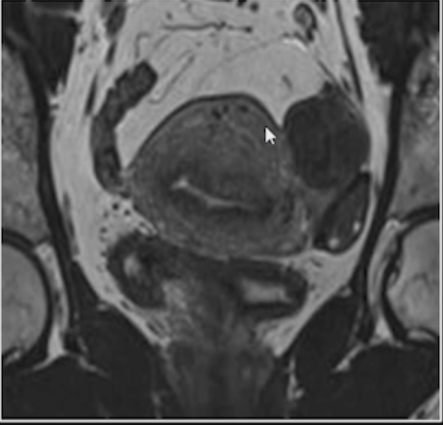

Mucocele de apêndice